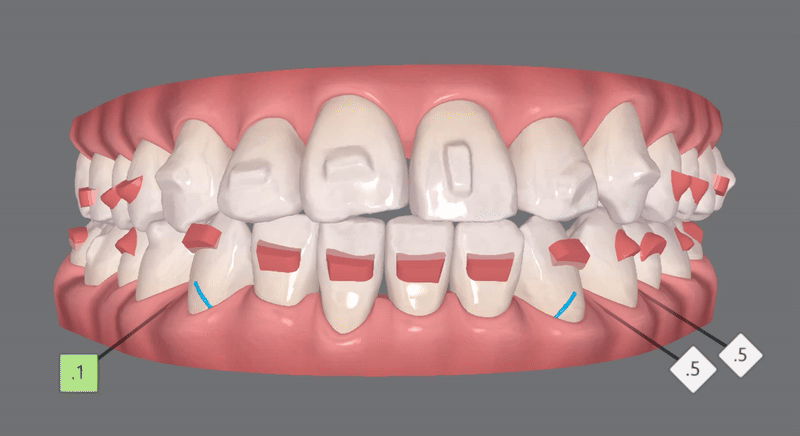

1st Clincheck(50개)

첫번째는 50개의 클린체크로 진행되었습니다.

악궁을 점점 확장시켜 생긴 공간에

안쪽으로 들어가있던 앞니들이

점점 제위치를 찾아갑니다 :)

발치 없이, 별도의 악궁확장장치 없이

교정이 가능한

송파인비절라인잘하는치과

잠실다이아몬드등급치과

인비절라인의 위력!

어떠신가요?